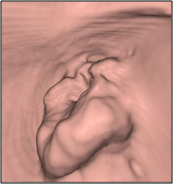

大動脈ステントグラフト

治療前   治療後